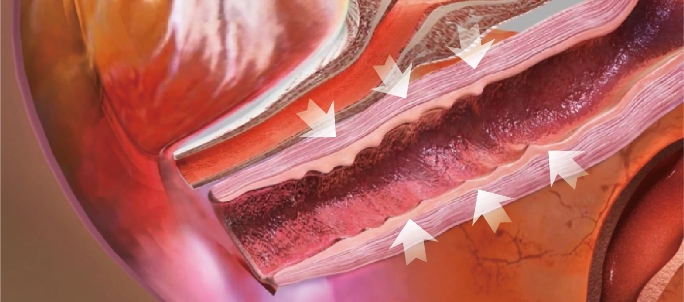

Thermal stimulation of entire vaginal wall layer

Immediately after treatment, shrinkage of the vaginal skin fibers occurs. In addition, collagen growth is promoted and the vaginal wall becomes resilient and thick. Changed Vaginal structure after treatments makes its whole conditions better.